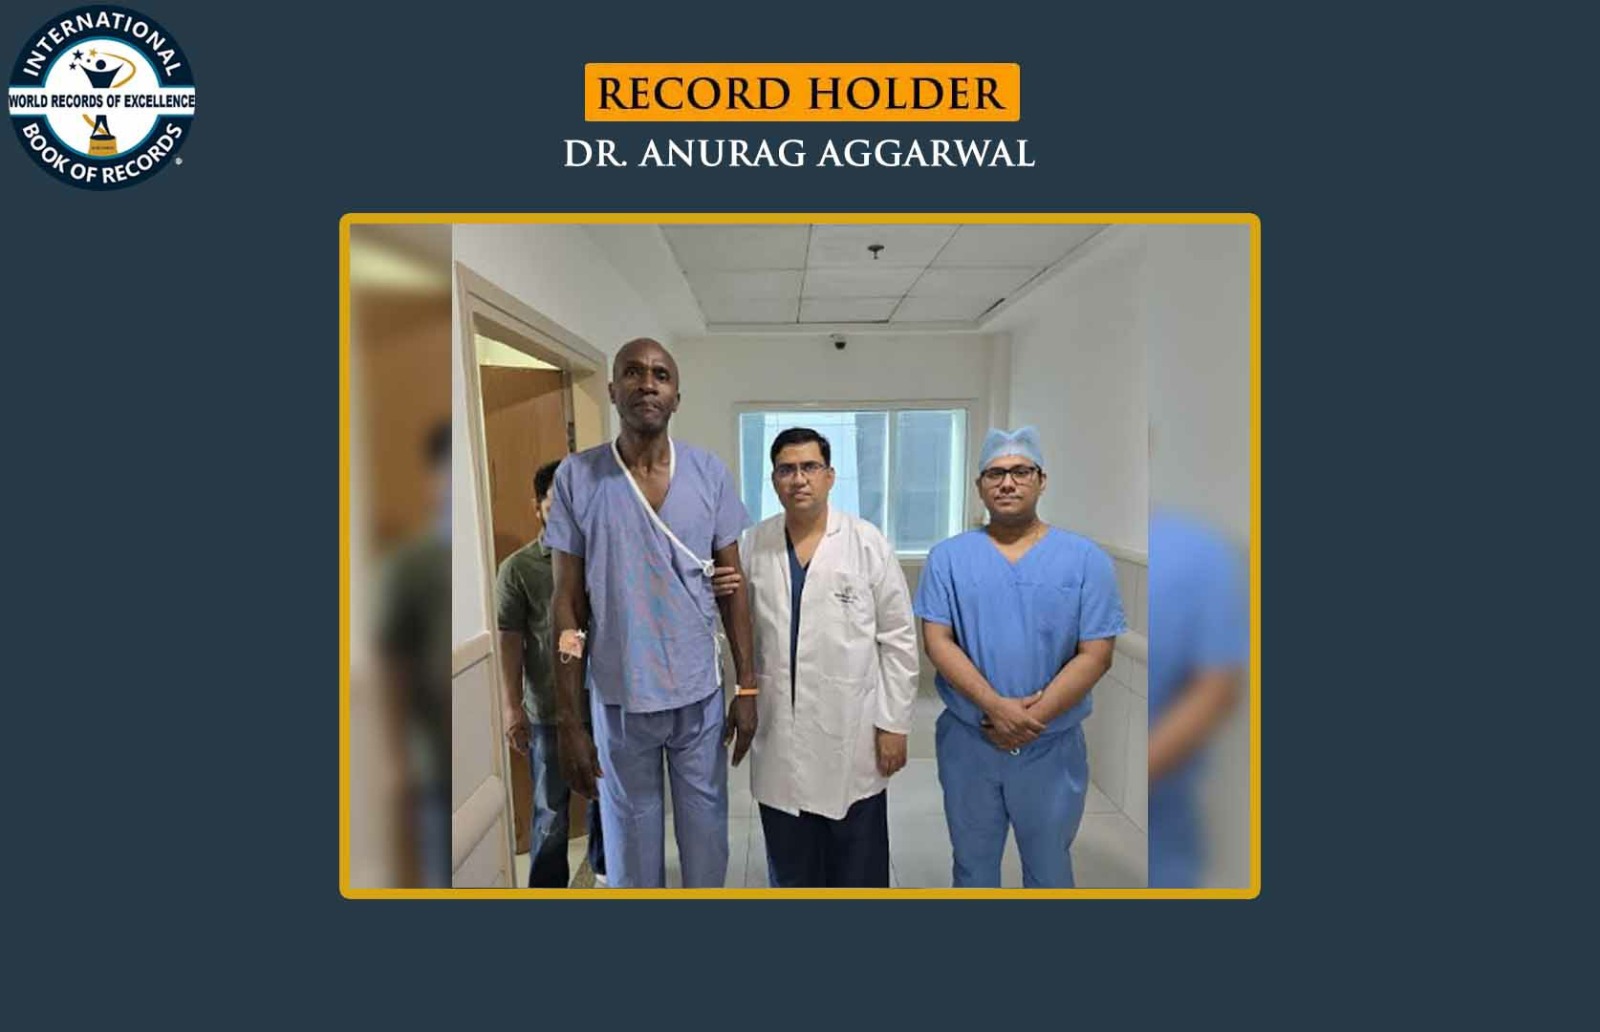

ROBOTIC BILATERAL KNEE REPLACEMENT PERFORMED ON THE TALLEST PATIENT WITH THE LARGEST IMPLANT SIZE

- Dr. ANURAG AGGARWAL (Haryana, India)About the Record

The World Record for “ROBOTIC BILATERAL KNEE REPLACEMENT PERFORMED ON THE TALLEST PATIENT WITH THE LARGEST IMPLANT SIZE” was achieved by Dr. ANURAG AGGARWAL on 20th July 2025 from Faridabad, Haryana, India. He successfully performed robotic-assisted bilateral knee replacement on a 197 cm tall person, using an H-sized femoral component and a tibial tray of size 8 and has set a new world record for International Book of Records.